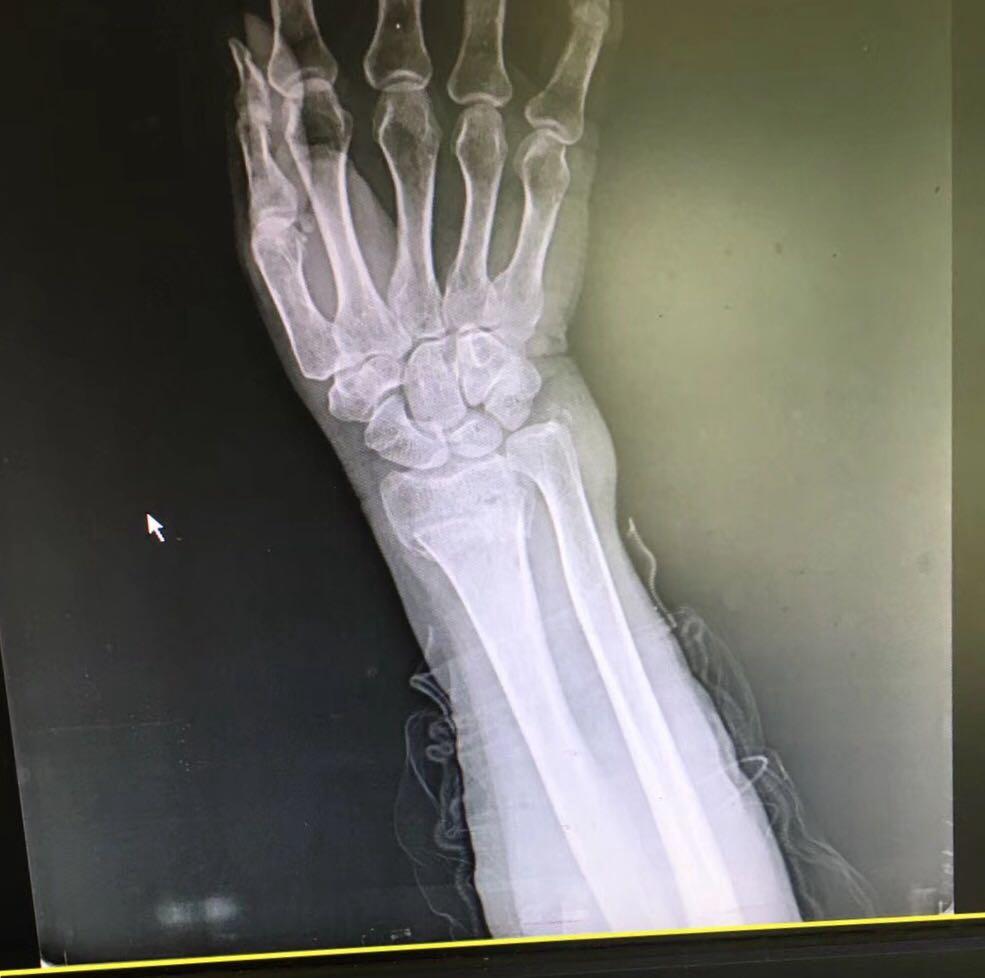

colles骨折求会诊

图片尺寸3264x2448